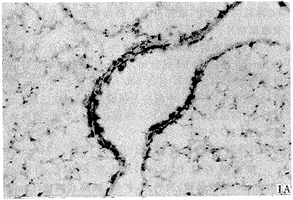

实验动物肺组织IL-5原位杂交结果镜下显示,哮喘时肺组织见较广泛阳性染色细胞,主要分布于气管粘膜下、肺泡间、甚至肺泡腔内。高倍镜下见阳性染色IL-5 mRNA定位于胞浆,呈紫蓝色,见图1。而D组与C组实验动物肺组织可见少许阳性染色细胞,见图2,3。表2示图像分析结果,A组肺组织IL-5 mRNA水平明显高于C组及D组(P<0.01),而D组IL-5 mRNA水平与C组相比差异不明显(P>0.05)。

图1 哮喘豚鼠肺组织IL-5 mRNA表达 A:ISH×100;B:ISH×400

Fig 1 IL-5 mRNA expression in lung tissue of asthmatic guinea pigs A:ISH×100;B:ISH×400